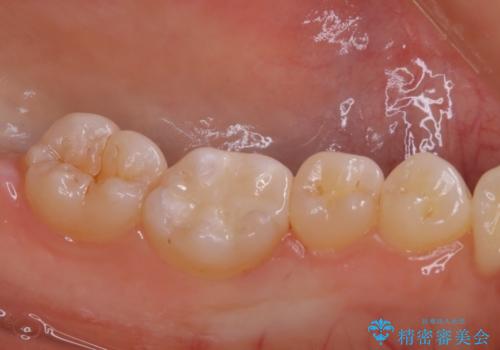

適合のよいセラミックで自分の歯となじむ自然な仕上がりに

- 大きく口を開けると目立つ銀歯のやり替えをご希望された患者様です。適合のよいセラミックインレーで補綴することで、将来的な虫歯発生のリスクを最小限に抑え、機能面でも安心して使っていただけるようにしました